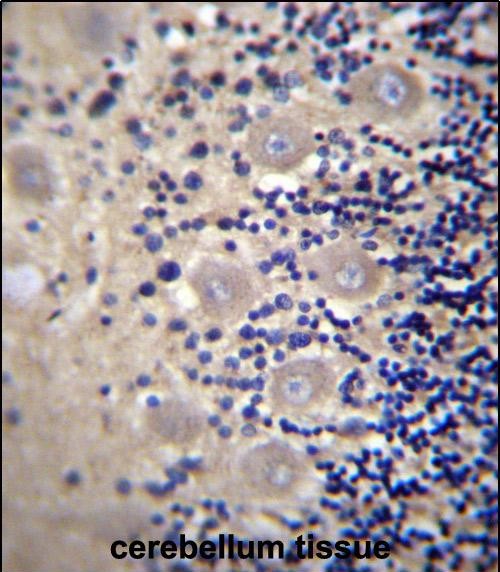

- DRG1 Antibody (C-term) (Cat. #P34600)immunohistochemistry analysis in formalin fixed and paraffin embedded human cerebellum tissue followed by peroxidase conjugation of the secondary antibody and DAB staining.This data demonstrates the use of DRG1 Antibody (C-term) for immunohistochemistry. Clinical relevance has not been evaluated.